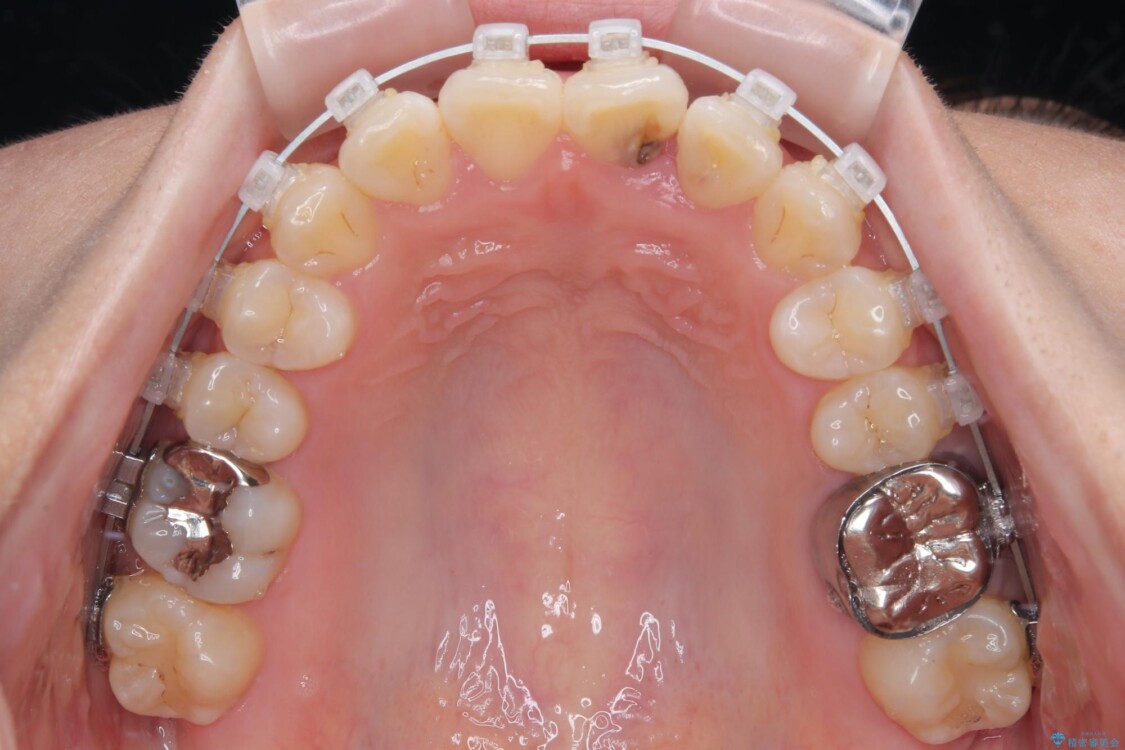

治療方法としては、装置の目立ちにくさと費用面のバランスを考慮して、プラスチック製のクリアブラケットとメタルワイヤーを組み合わせた矯正装置を使用することにしました。

また、上顎前歯の重なっていた部分にはむし歯が見つかり、治療中に適切な処置を行っています。

治療途中

• 前歯のねじれ・ガタガタを10か月で改善!20代女性の矯正治療|クリアブラケットでむし歯になりにくい歯並びへ改善 治療途中画像